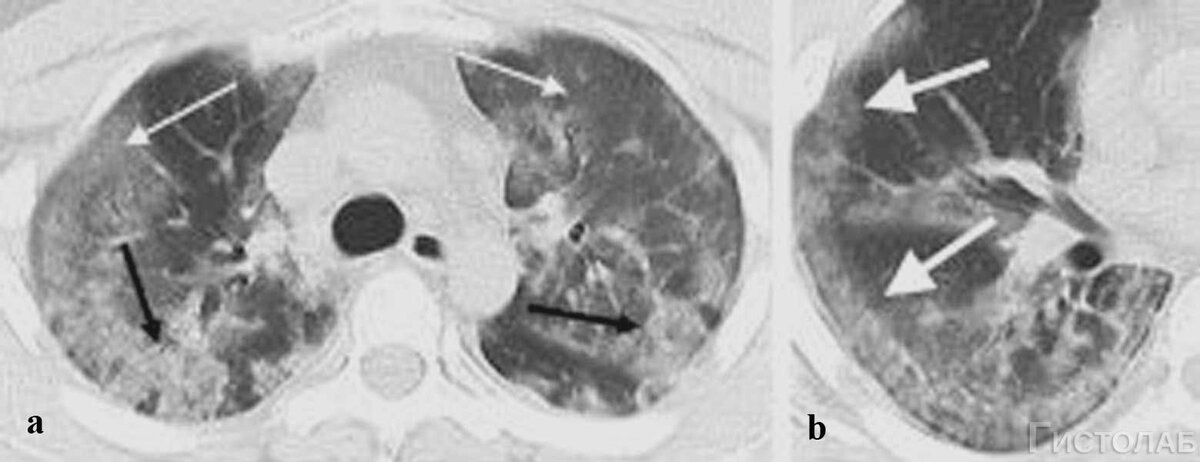

Вирусное поражение легких

При этом часто повреждаются мелкие сосуды, поэтому поражение легочной ткани имеет рассеянные характер. Вот почему на рентгеновских снимках и МРТ мы видим такую картину. Она полностью отличается от картины привычной пневмонии.